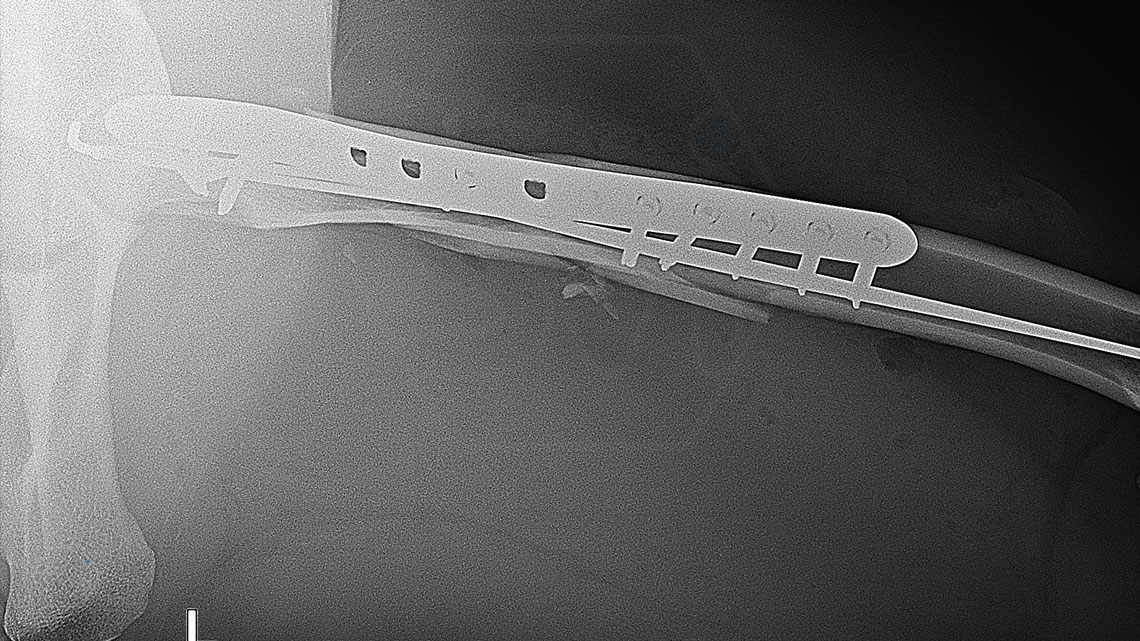

The 9-year-old female cheetah broke her leg so miserably near the femoral neck during a regrouping. Here again, the combination of the intramedullary pin and polyaxial lockin plate mentioned in the previous post was used to fix the fracture. During the screw insertions into the proximal piece, the polyaxiality came in really handy, we were able to avoid the 2.5 mm K-nails with the long screws. I hope the 14-hole 12 * 4 mm wide polyaxial plate (which could have been longer…) will be long enough, with a mix of 4.0 and 3.5 mm screws for maximum stability. From below, screw 6 is a cortical screw that secures a larger contralateral fragment as a lag screw.

Thus, 3 screws of different thicknesses (3.5 and 4.0 polyaxes) and shapes (AO screws) were placed in the plate, while ONE screwdriver was used because each has a hex head.